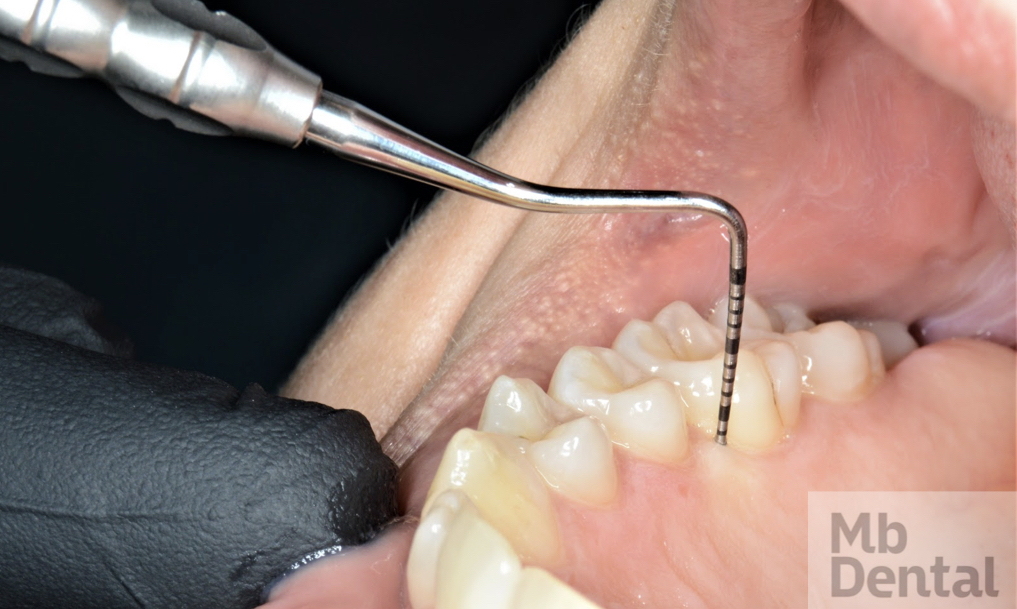

Dacă aveți vreo suspiciune că aveți o suferință de natură parodontală, sau dacă medicul dumneavoastră stomatolog observă o asemenea afecțiune, primul pas este o vizită la medicul parodontolog. Acesta vă va efectua un consult complet, însoțit de realizarea unei fișe parodontale, ce va urmări măsurarea gingiei din jurul fiecărui dinte, conform imaginii alăturate. În funcție de aceasta, se va pune un diagnostic și se va recomanda un plan de tratament aferent.

Consultatie parodontologica